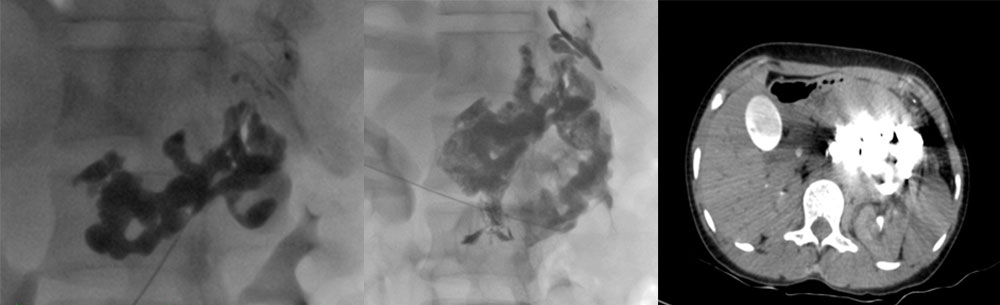

Pre-operative embolization is a medical procedure that is used to block blood flow to a specific area of the body. The purpose of this procedure is to prevent blood from flowing to an area that is going to be operated on. This can be done by injecting a substance into the blood vessels that lead to the area to be operated on. This substance will then block the blood flow and prevent it from reaching the area.

Pre-operative embolization is typically used when a patient is going to have surgery on an organ or area that is located near a major blood vessel. This procedure can also be used to prevent blood from flowing to an area that has been damaged by an injury. In some cases, pre-operative embolization may also be used to treat a tumor.

There are a number of different substances that can be used for pre-operative embolization. The most common substance that is used is a gel foam. This gel foam is injected into the blood vessels and will then expand to block the blood flow. Other substances that can be used include beads, coils, and plugs.